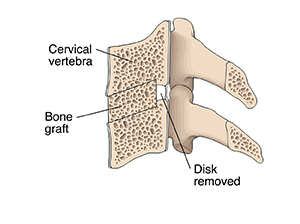

The disk is removed from between the vertebrae to be fused.

A bone graft or intervertebral implant filled with bone is placed into the now-empty space between the vertebrae. Screws, plates, or a plate with screws are often placed in to ensure additional stability. In time, the graft and the bone around it will grow into a solid unit.